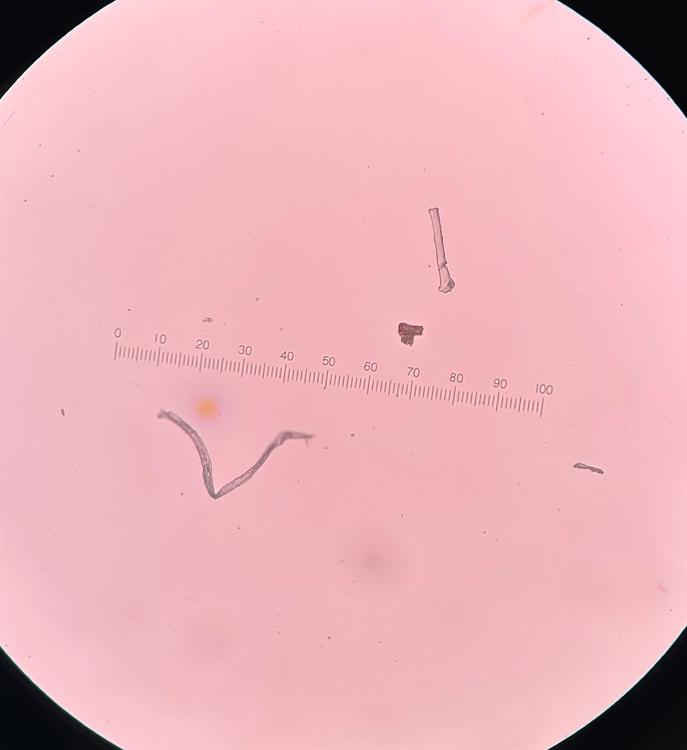

Necator larvae

Strongyloides larvae